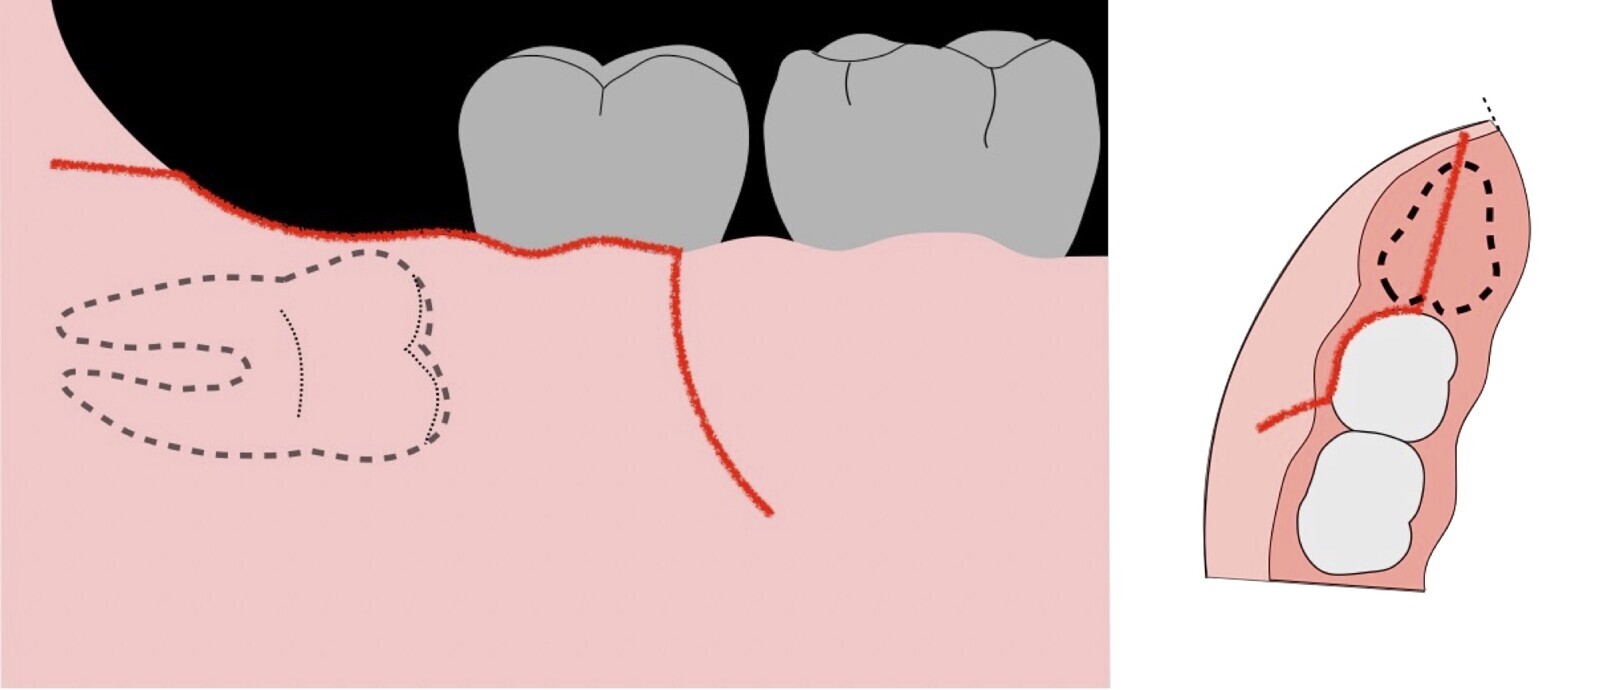

El procedimiento se inicia colocando anestesia troncular para bloqueo del nervio dentario inferior y sus ramas. Luego, se establecerá el diseño de acceso según la disposición de la molar a extraer. Para fines didácticos, se explicará cómo se realizaría la extracción de la molar de la Figura 1: se realiza una incisión horizontal a nivel de la zona retromolar hasta llegar a distal de la segunda molar, continuándose con una incisión intrasurcular hasta mesial de la segunda molar, finalizando con una incisión vertical a espesor total hasta llegar a la línea mucogingival (Figura 2).

Figura 2. Diseño de incisión para el acceso a la tercera molar.

Figura 3. Decolado a espesor total para el acceso a la tercera molar.